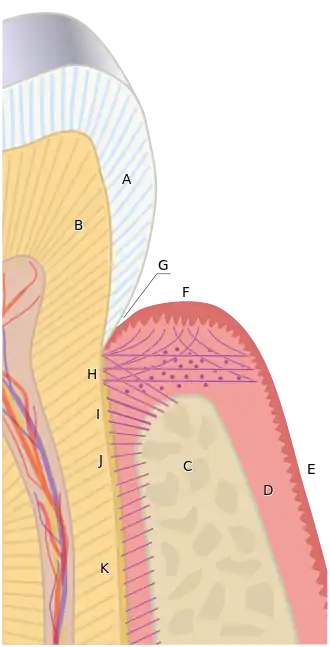

Supracrestal tissue attachment

Previously known as biologic width,[5] supracrestal tissue attachment (STA) consists of the junctional epithelium and connective tissue attachment above the alveolar crest.[6] On average, STA is 2.04 mm, with the junctional epithelium and connective tissue constituting 0.97 and 1.07 mm, respectively.[2][7] However, the STA has been observed to vary between 0.75 - 4.33 mm.[8]

It is important to avoid invading the STA when fabricating dental restorations. If a dental restoration invades the STA, chronic inflammation is likely to occur which then causes pain, gum recession, and unpredictable loss of alveolar bone.[9][10][11]

Due to the variation in STA and limits of precisely restoring a tooth to the coronal edge of the junctional epithelium, it is often recommended to remove enough bone to place restorative margins such that they maintain at least 3 mm of tooth and gum tissue above the alveolar crest.[12][13][14]